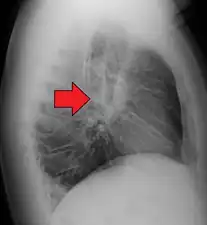

| Chest X-ray showing the typical nodularity of sarcoidosis, predominantly in the hila of the lungs. | |

Chest radiograph changes are divided into four stages:[105]

- bihilar lymphadenopathy

- bihilar lymphadenopathy and reticulonodular infiltrates

- bilateral pulmonary infiltrates

- fibrocystic sarcoidosis typically with upward hilar retraction, cystic and bullous changes

Although people with stage 1 radiographs tend to have the acute or subacute, reversible form of the disease, those with stages 2 and 3 often have the chronic, progressive disease; these patterns do not represent consecutive "stages" of sarcoidosis. Thus, except for epidemiologic purposes, this categorization is mostly of historic interest.[28]

Hilar adenopathy especially on the person's left (lateral CXR)